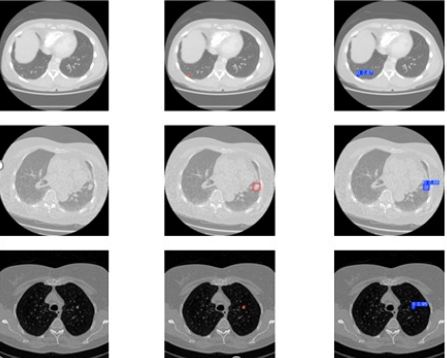

Early Detection and Classification of Lung Cancer using Segment Anything Model 2 and Dense Net

Hafza Eman, Syed M. Adnan, Wakeel Ahmad, Ishtiaque Mahmood

479-492